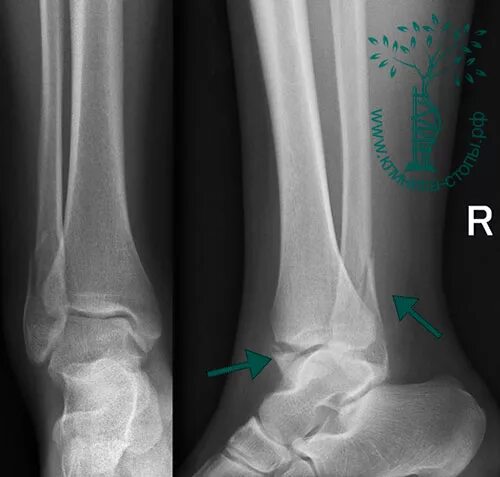

Заросший перелом со смещением